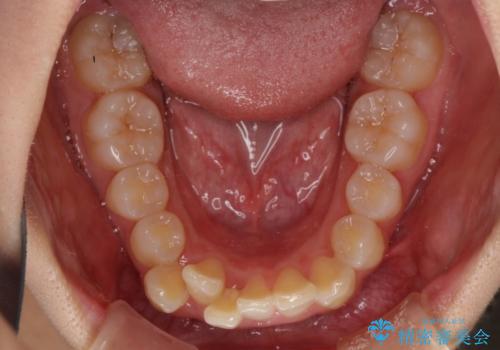

- 前歯のデコボコ気になるとのことで来院された患者様です。

上下顎ともに歯列全体の後方移動とIPR(歯と歯の間を削る)によってデコボコが解消するように設計し、インビザラインにより治療を行うこととしました。